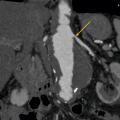

L’échographie-Doppler, l’angio-tomodensitométrie (angio-TDM [fig. 2] et l’angio-imagerie par résonance magnétique (angio-IRM) [fig. 3] permettent le diagnostic de sténose de l'artère rénale. Ils estiment à la fois le degré de sténose (exprimé en pourcentage de réduction du diamètre) et l’impact sur la vascularisation d’aval. Ces 3 examens sont validés et recommandés en première intention. Leur utilisation dépend de l’accessibilité et des habitudes locales. Il est à noter que l’écho-Doppler, très sensible et spécifique dans la sténose de l'artère rénale athéromateuse sous réserve d’un opérateur entraîné, est de sensibilité imparfaite dans la fibrodysplasie, dans laquelle l’angio-TDM est l’examen de référence.

Dans la sténose de l'artère rénale athéromateuse, on retrouve une plaque habituellement unique, plus une moins calcifiée, ostiale, proximale ou tronculaire, responsable d’une réduction du diamètre endoluminal d’une ou des artères rénales (fig. 2 et 3).

En cas de fibrodysplasie, les lésions sont multiples, distales, souvent bilatérales, avec aspect en « collier de perles » (fig. 4). Il est recommandé, dans cette pathologie qui est souvent multifocale, de rechercher d’autres lésions artérielles (sténoses ou anévrismes) au niveau des artères digestives, cervicales et intracrâniennes.